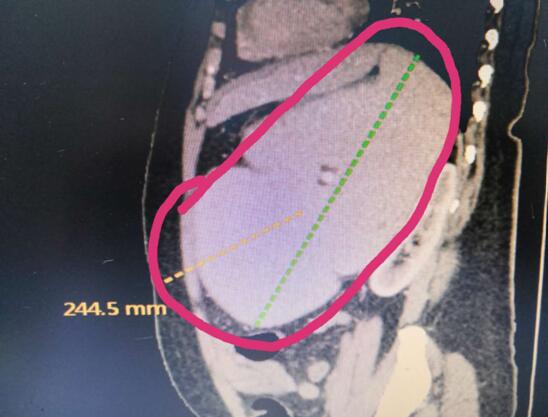

患者A,女,72歲,1年前因急性出血壞死性胰腺炎,曾行腹腔鏡下壞死胰腺組織清創(chuàng)+外引流術(shù),術(shù)后出現(xiàn)急性胰腺假性囊腫,囊腫越來越增大,以至于病人不能做下蹲和彎腰動作,給生活造成極大不便。本次患者因急性腹痛入院,入院診斷為:胰腺巨大假性囊腫并發(fā)出血,重癥胰腺炎清創(chuàng)術(shù)后。

(術(shù)前腹部CT顯示胰腺巨大假性囊腫)